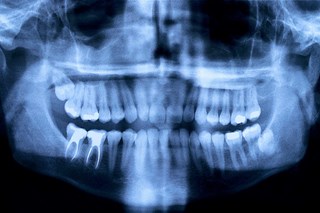

Behandlingar

Nedan finns en lista med behandlingar som vi utför. Klicka på knapparna för att läsa mer om just den behandlingstypen🦷